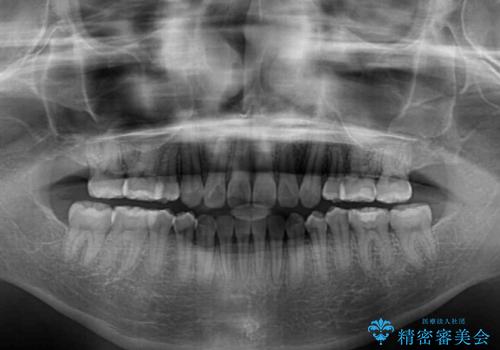

話しにくいオープンバイト ワイヤー装置による抜歯矯正治療

- 前歯のオープンバイトを気にして来院された患者様です。

上下前歯の前後位置が大きくずれていたため、上顎左右第一小臼歯2本を抜歯してワイヤー装置による矯正治療を行うこととしました。

オープンバイトの原因は舌の突出癖であり、癖が改善されないと治療経過に影響を及ぼすため、舌のトレーニングを指示しました。

なかなか癖が改善されず、トレーニングも断続的に行ったため、治療期間は長期化しました。